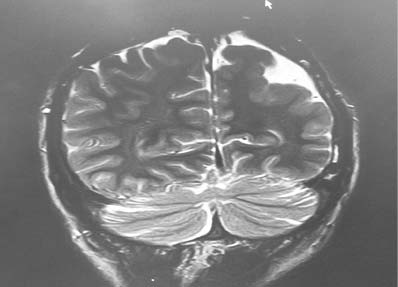

При МРТ головного мозга (1,5 Тл) выявлены утолщение коры и увеличение количества извилин — полимикрогирия (рис. 2).

Рис. 2. Данные магнитно-резонансной томографии головного мозга обследованного пациента: полимикрогирия